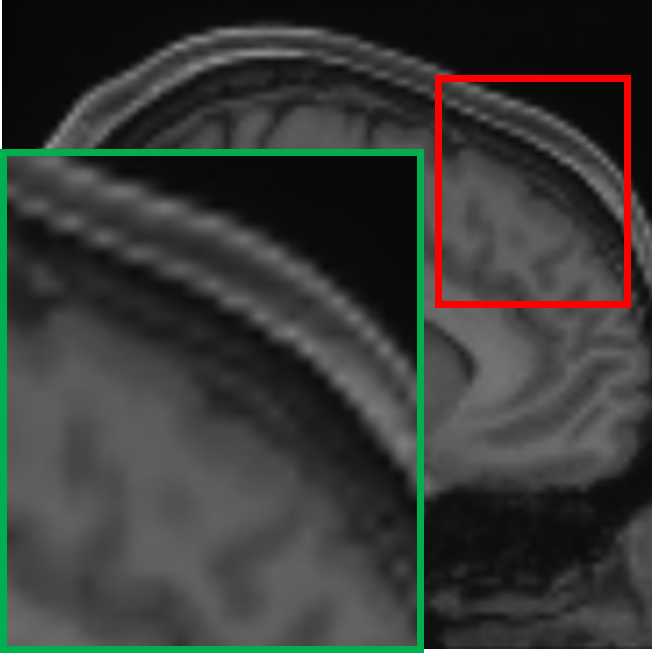

IV-C Visualization of the expert specialization

To further elucidate the functional specialization of each expert within the proposed MoE framework, we visualize the difference maps between each expert’s output and the ground truth 7T MRI. These maps are computed by taking the pixel-wise absolute difference between the expert output and the ground truth 7T MRI, highlighting the residual discrepancies and reconstruction focus of each expert. In the visualizations, lighter areas reflect lower reconstruction errors, suggesting better alignment with the ground truth. As shown in Fig. IV, each column represents the output of a particular expert, visualized through its corresponding absolute difference map with respect to the 7T reference. The final output is computed via a weighted combination of expert outputs. The visualized difference maps underscore the distinct specialization of each expert. Specifically, Expert 1 exhibits minimal residuals in homogeneous white matter regions, preserving large-scale anatomical continuity. Its low-frequency focus is evident in the smooth residual patterns and coherent structural boundaries. Expert 2 demonstrates heightened sensitivity to cortical regions and sulcal boundaries, with pronounced residual suppression around edges and high-frequency details. Expert 3 shows enhanced reconstruction accuracy at tissue interfaces and transitional zones. The residuals are particularly reduced in regions of sharp contrast changes. These observations confirm that each expert effectively targets specific anatomical and textural characteristics, guided by their unique architectural and loss function design. The gating mechanism further facilitates optimal integration by adaptively weighting expert contributions according to the local image context, thus ensuring a globally coherent and anatomically faithful 7T-like reconstruction.

TABLE IV: Visualization of the expert specialization

E1subscript𝐸1E_{1}italic_E start_POSTSUBSCRIPT 1 end_POSTSUBSCRIPT E2subscript𝐸2E_{2}italic_E start_POSTSUBSCRIPT 2 end_POSTSUBSCRIPT E3subscript𝐸3E_{3}italic_E start_POSTSUBSCRIPT 3 end_POSTSUBSCRIPT Final

[Uncaptioned image] [Uncaptioned image] [Uncaptioned image] [Uncaptioned image]

𝒢1=0.21subscript𝒢10.21\mathcal{G}_{1}=0.21caligraphic_G start_POSTSUBSCRIPT 1 end_POSTSUBSCRIPT = 0.21 𝒢2=0.48subscript𝒢20.48\mathcal{G}_{2}=0.48caligraphic_G start_POSTSUBSCRIPT 2 end_POSTSUBSCRIPT = 0.48 𝒢3=0.31subscript𝒢30.31\mathcal{G}_{3}=0.31caligraphic_G start_POSTSUBSCRIPT 3 end_POSTSUBSCRIPT = 0.31 Weighted

• *

The expert-specific weights (𝒢1subscript𝒢1\mathcal{G}_{1}caligraphic_G start_POSTSUBSCRIPT 1 end_POSTSUBSCRIPT, 𝒢2subscript𝒢2\mathcal{G}_{2}caligraphic_G start_POSTSUBSCRIPT 2 end_POSTSUBSCRIPT, 𝒢3subscript𝒢3\mathcal{G}_{3}caligraphic_G start_POSTSUBSCRIPT 3 end_POSTSUBSCRIPT) for this particular slice are dynamically computed by the gating network 𝒢𝒢\mathcal{G}caligraphic_G.